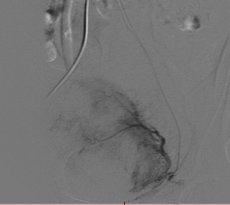

Bei der Embolisation wird über die Leiste ein sehr dünner Schlauch (Katheter) in die Arterie eingeführt und unter Röntgenkontrolle von einem spezialisierten Radiologen bis zur Gebärmutterarterie vorgebracht. Dort werden feinste Kügelchen (Microsphären) in die Myome gespritzt, so dass diese absterben und die Beschwerden verschwinden. Die Gebärmutter selbst bleibt erhalten.